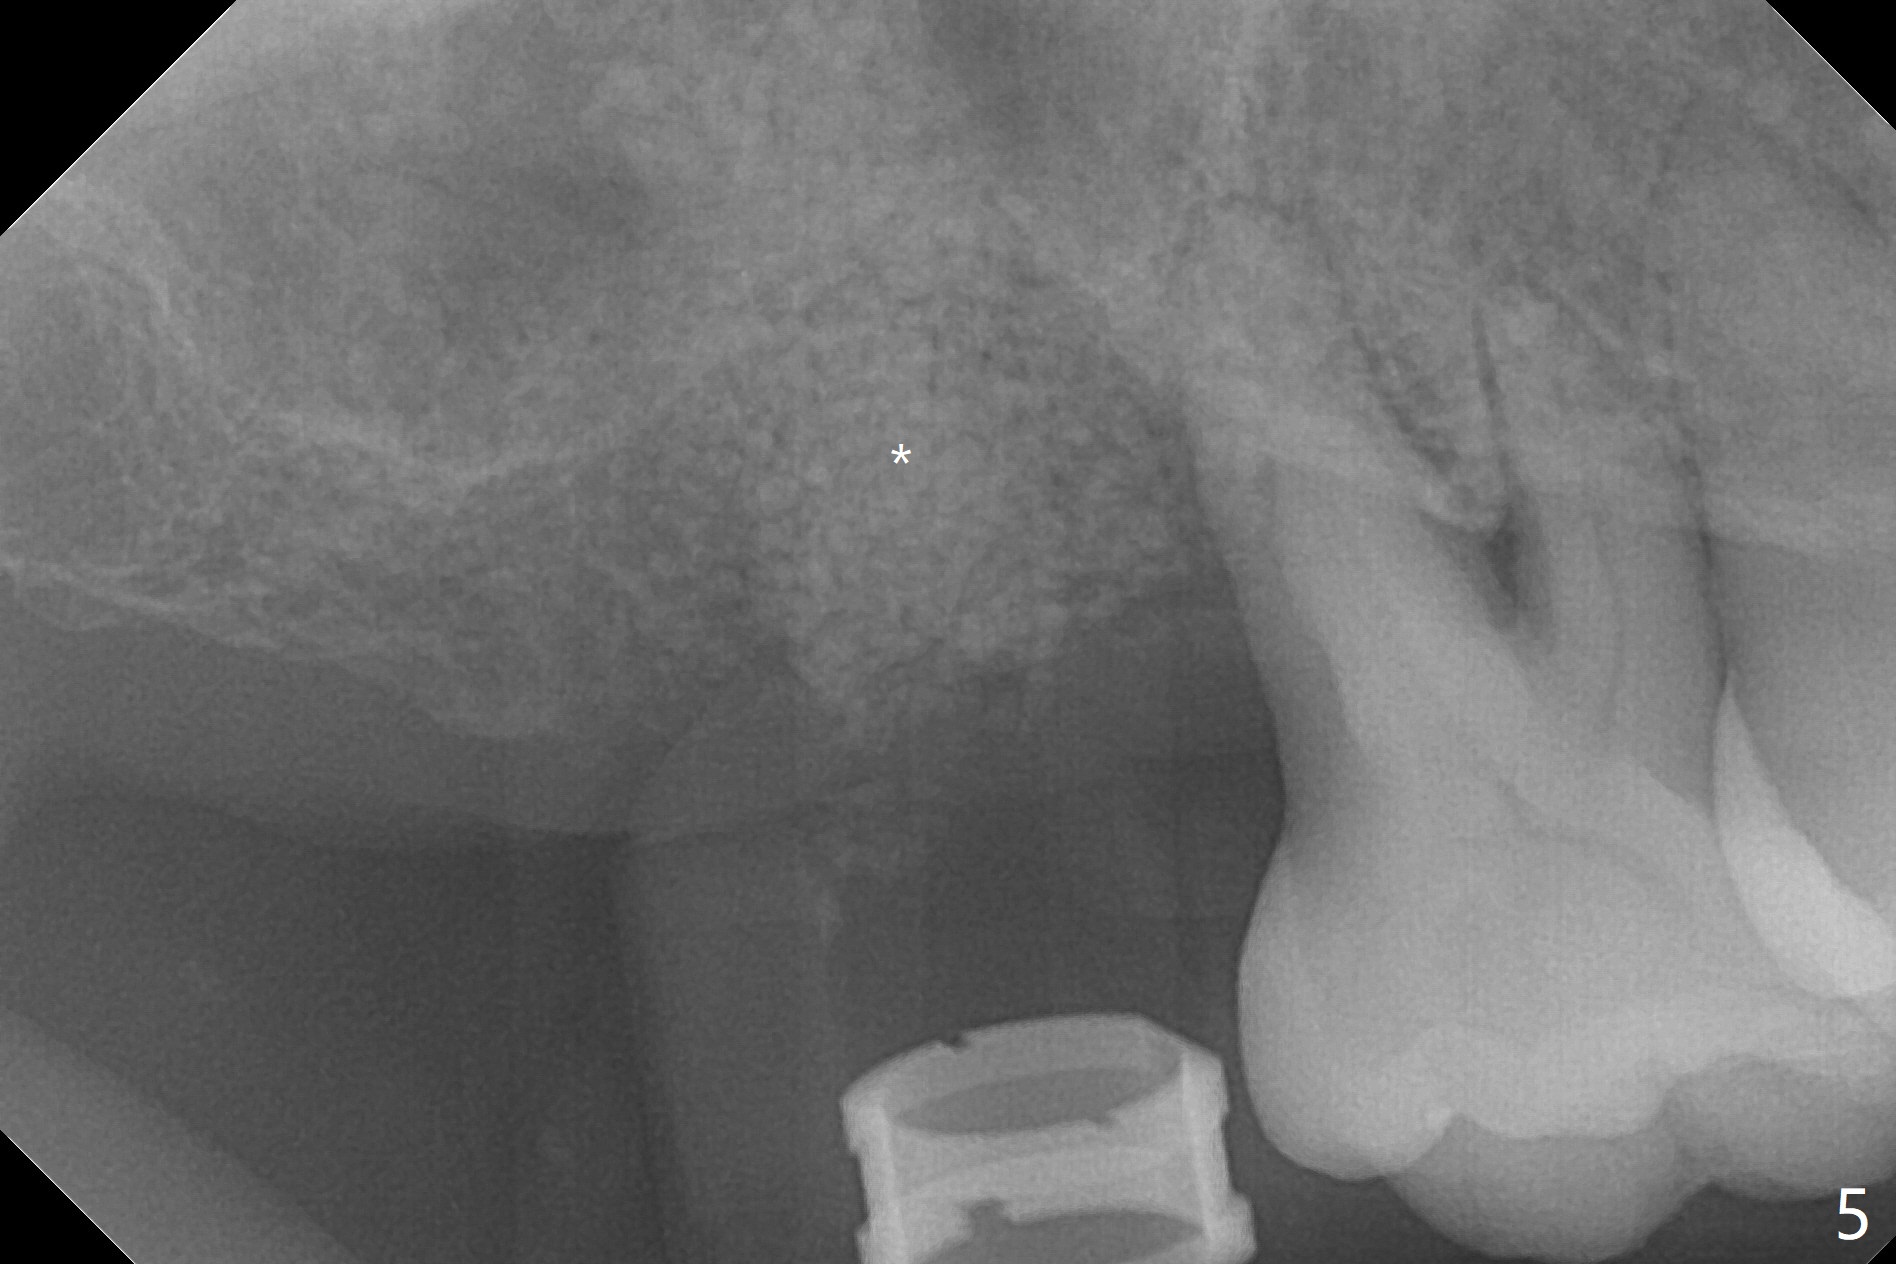

45岁女右上7严重骨质吸收,位点保存4-5个月,骨质高度增加,但是密度好像下降,准备上颌窦内提,同期种植,如果扭力太低,使用愈合帽,关闭伤口,最简易方法是利用环形刀保留牙龈。首先利用导板和导板环形刀(图一:好像绞肉机)在牙龈表面轻轻做一个标记(用手顺着金属圈按一下),然后取出导板,徒手使用锐利活检环形刀(图二),取出圆形牙龈,放入PRF上清液备用(图三)。接着放回导板完成提升(图四:*),不幸的是大一号正式植体无法取得稳定性,不得不取出,再大一号报废植体也无能取得固定,只好植骨(图五:*),放回保留的牙龈(图六:*),使用牙周胶水和树脂敷料固定。其实植骨前发现窦膜破裂,不过术后没有上颌窦并发症(术后服用激素)。术后7天树脂敷料稳定,局部卫生尚可(图七),准备术后一个月撤除敷料。